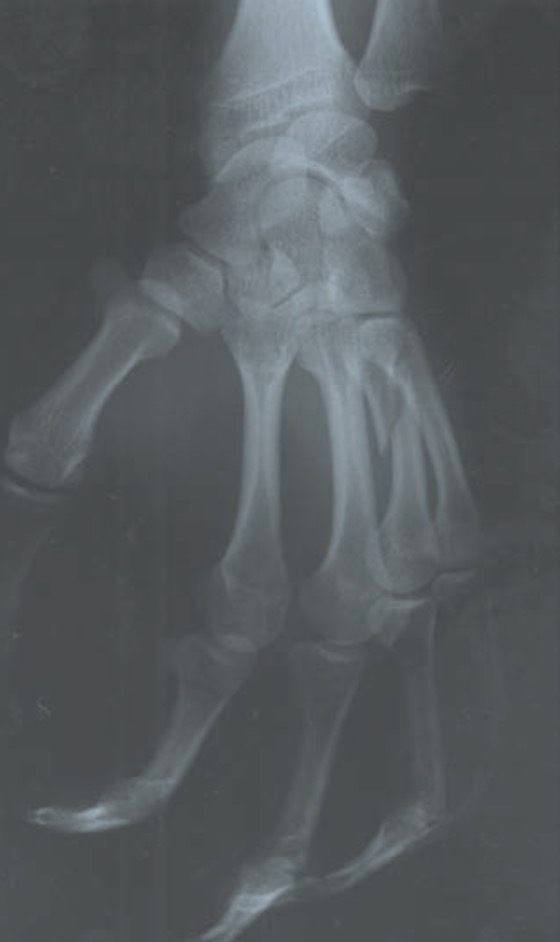

At the hospital, stripped naked of my garments with scissors, after X-Rays I’m told I’ve fractures in my hip and a broken bone in my left hand. The latter is a spiral fracture which narrowly avoids being wired up. I’m a very lucky man. The consultant compares my hip to a Polo mint. How often can you crack one side without the whole thing splitting in two? I’ve cracked the iliac crest, which is the ‘wing’ of the hip – the part that would sit above the belt line. Amazingly, I’ve avoided damaging the femur joint, or splitting my pelvic girdle in two. There is a crack snaking its way through towards the sacroiliac joint, but I am told my hips are stable and I should try to get onto crutches.